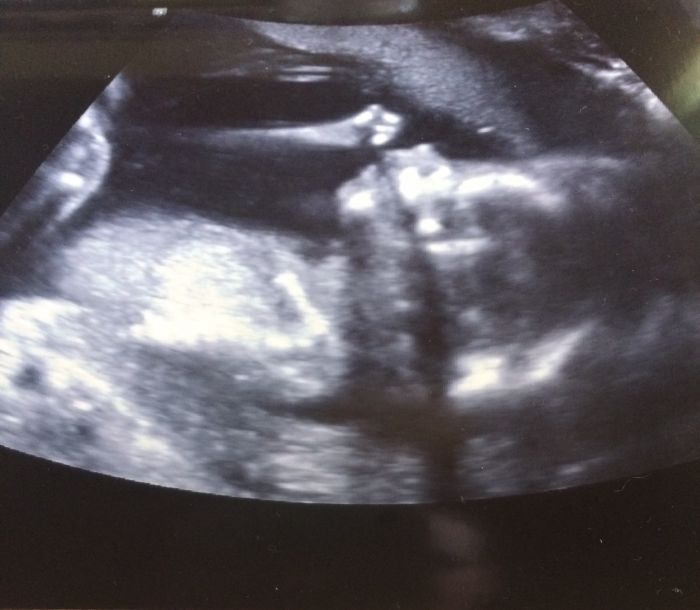

Ahoj holky, mám po poradně, jsem v 18tt, miminko roste, srdíčko bije a vše vypadá v pořádku. Mám v pořádku i krevní testy, moč i tlak a vidět toho tvorečka, bylo super:-), potvrdili mi holčičku a za 3 týdny jdu na druhý screening.